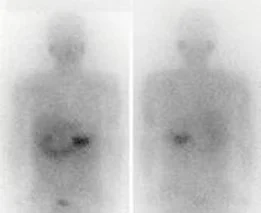

I-123 MIBG

This study requires injection of the radiopharmaceutical I-123 MIBG. The radiopharmaceutical will identify neuroendocrine tumors with the use of a gamma camera. Imaging is performed at 24 hours post injection and occasionally at 48 hours. A number of medications may interfere with this test so the patient may be asked to delay or discontinue some of them prior to the test. A complete medication list should be provided at the time of the scan.